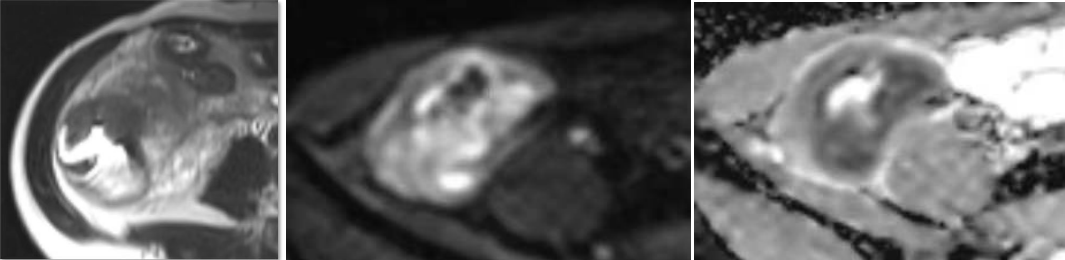

患者磁共振小肠造影情况

在李雪华教授的指导下,影像科团队详细地评估了患者肠壁增厚和肠腔狭窄的严重程度,对炎症性肠病影像的主要征象进行了规范化描述,从影像图像中判断有无相关并发症发生的可能,真正做到了病变的精准定位、定性,为患者进一步临床诊断治疗提供了明确的重要依据。